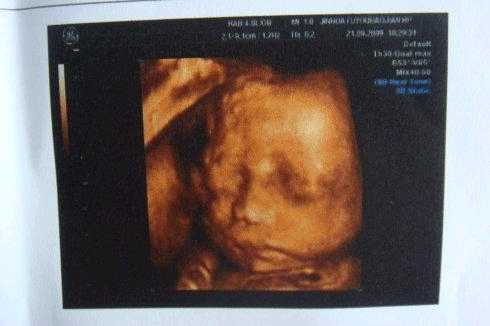

而小排畸和大排畸的区别在检查的方式、时间、目的上,大排畸是在妊娠18—24周做,主要是通过彩超成像的方式来观察胎儿的面部、体表及内脏各器官的发育情况。

30周4天的小排畸检查

而小排畸的检查方式一般会使用高分辨力的彩色多普勒血流显像仪检查,主要是四维彩超一般黑白B超只要求进行上述常规超声检查内容,一般不用黑白B超进行详细系统胎儿畸形超声检查。

小排畸检查在30周左右

一般大排畸都是采用的四维彩超检查,主要观察染色体异常标记,监测胎儿在宫内的发育情况。而小排畸只需做普通B超就可以,因为此时胎儿已经到了孕晚期,通过普通B超就能看到是否存在异常。